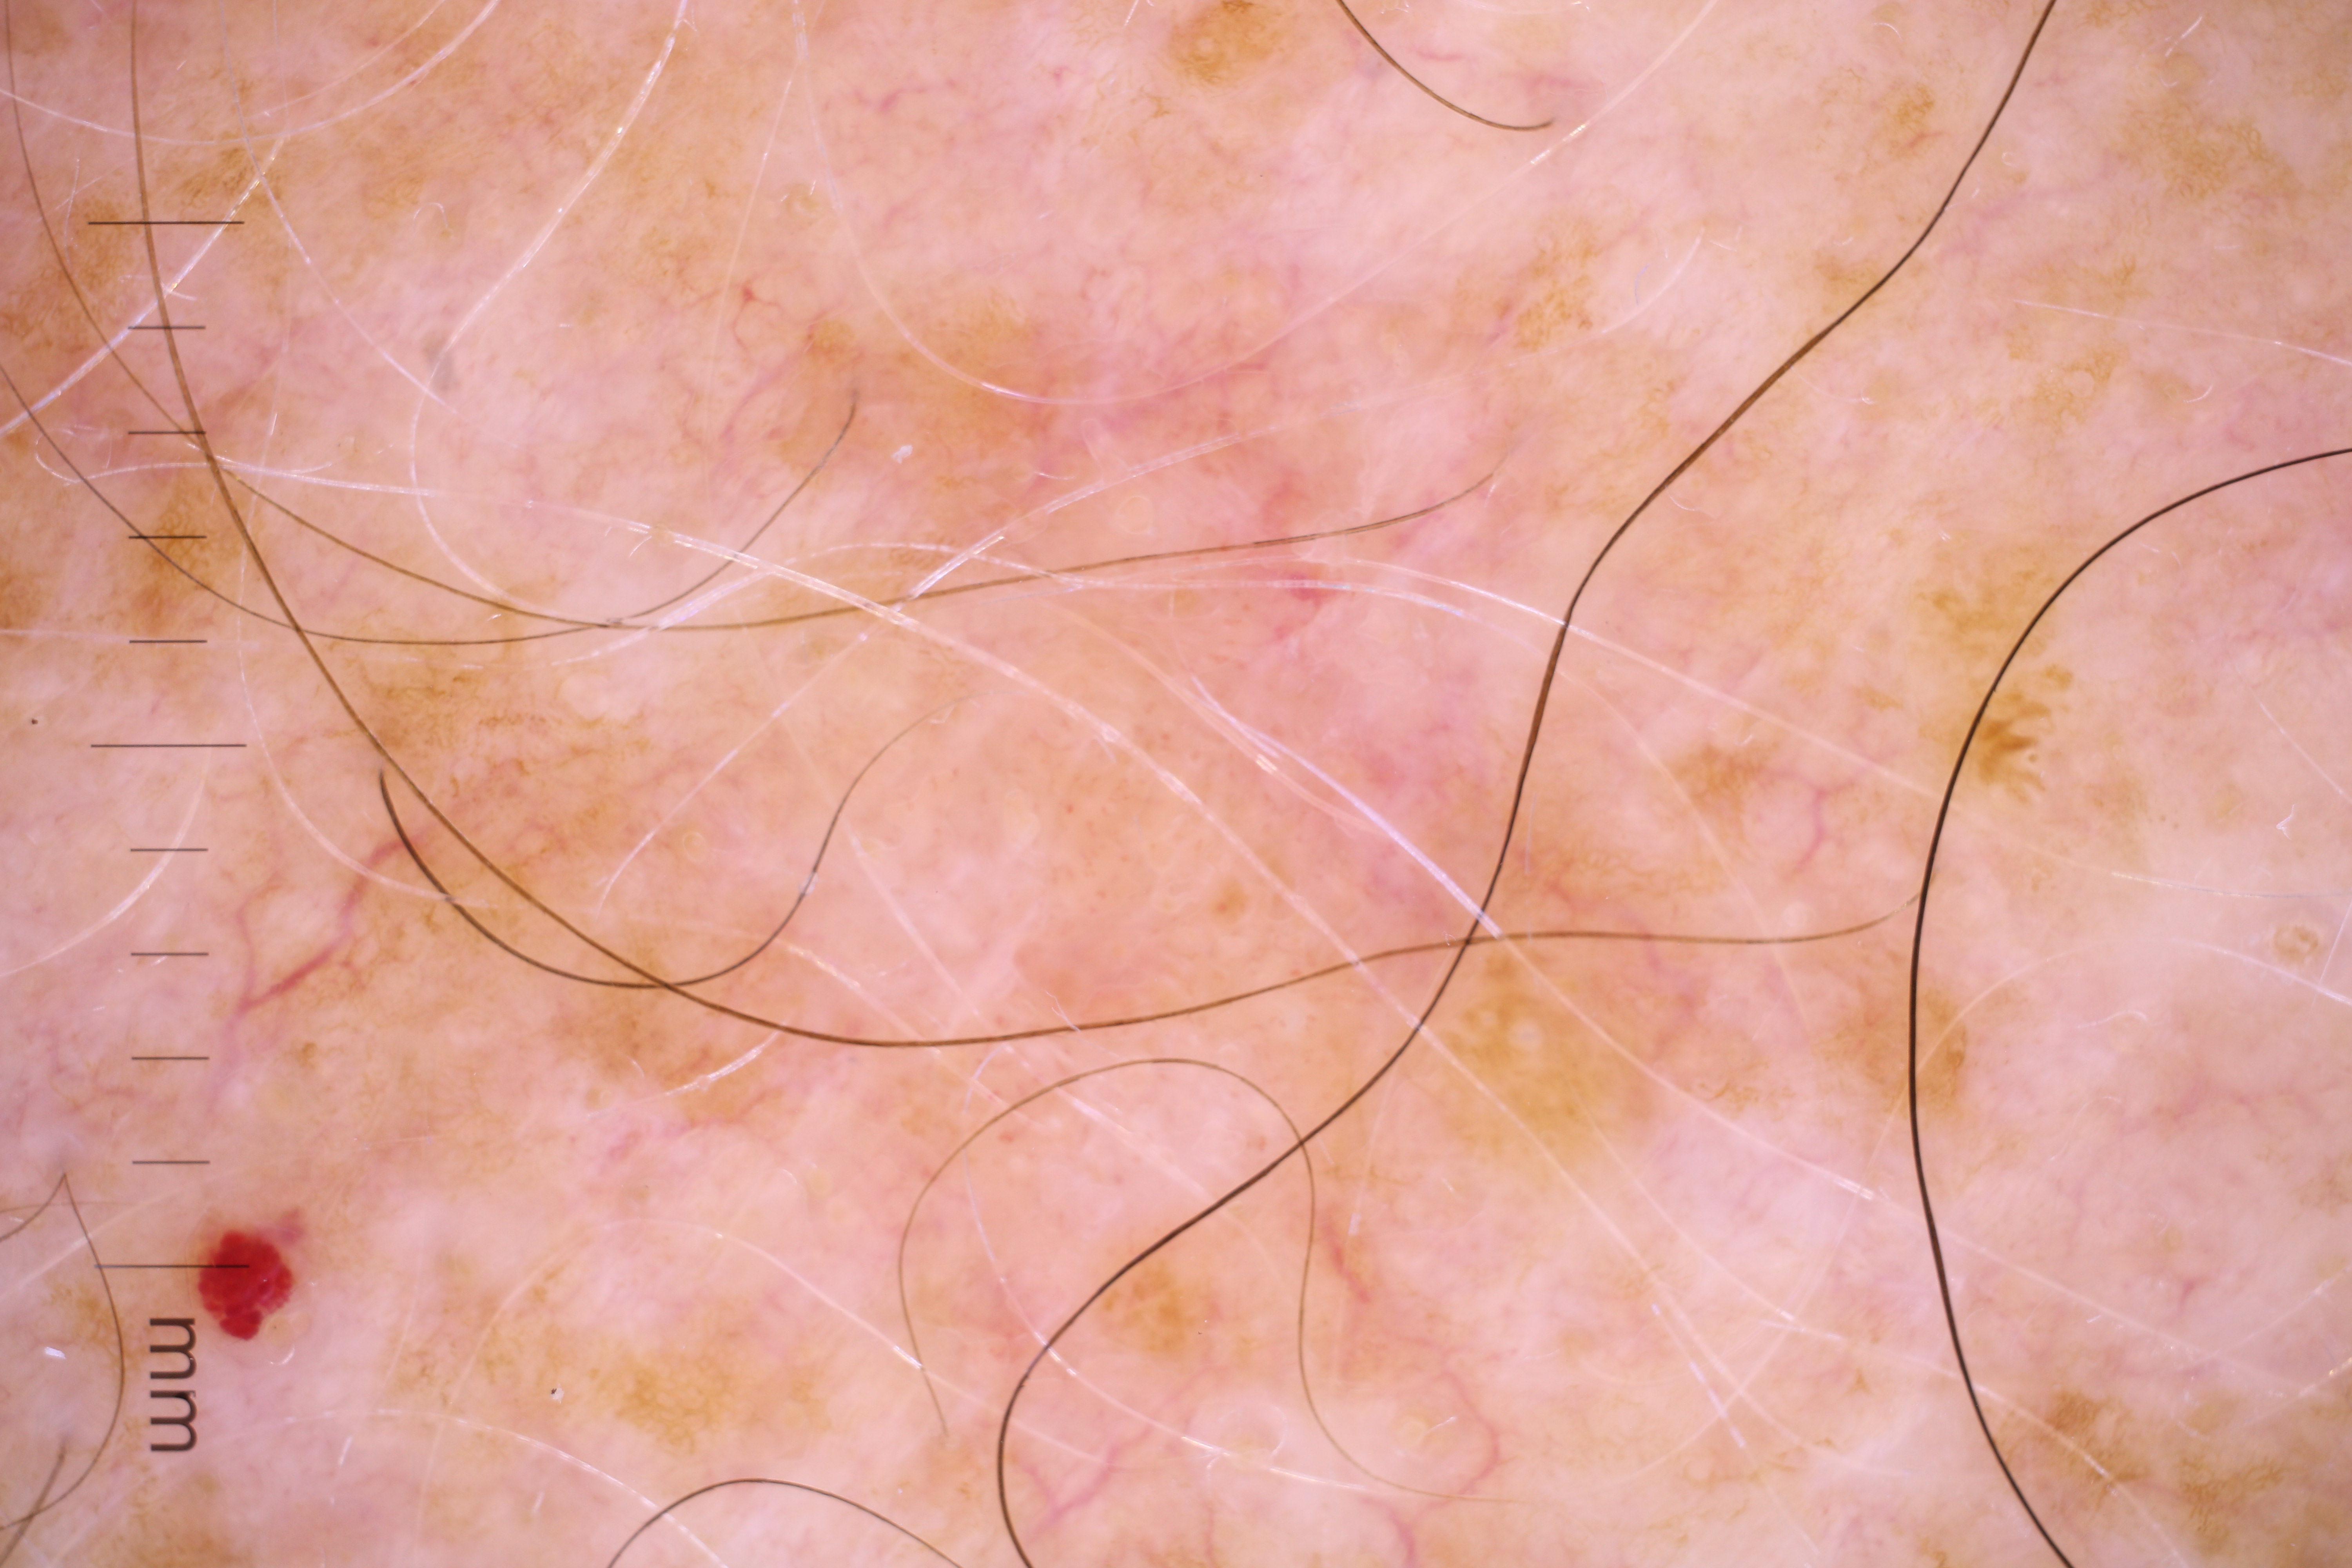

{

"acquisition_day": 551,

"age_approx": 60,

"anatom_site_general": "head/neck",

"concomitant_biopsy": false,

"dermoscopic_type": "contact non-polarized",

"diagnosis_1": "Benign",

"diagnosis_confirm_type": "serial imaging showing no change",

"image_type": "dermoscopic",

"lesion_id": "IL_9018983",

"patient_id": "IP_8003017",

"personal_hx_mm": true,

"sex": "female"

}